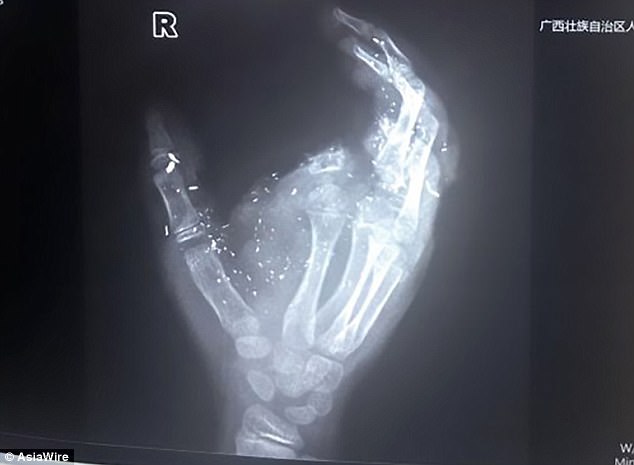

Hình chụp X-quang bàn tay bị tổn thương của Jisu.

Điện thoại bị nổ được xác nhận là chiếc Hua Tang VT-V59, sản xuất tại Trung Quốc. Hình ảnh X-quang cho thấy bàn tay cầm điện thoại của em bị tổn thương nặng nề. Chị gái của Jisu nói rằng sau khi nghe tiếng nổ lớn, cô vội vàng chạy vào thì thấy em trai mình dính đầy máu và mất ý thức ngay sau đó.